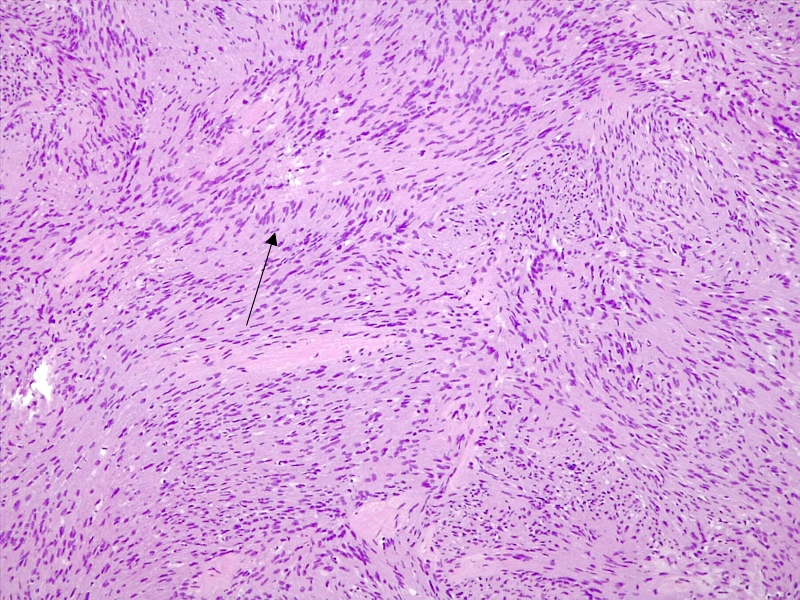

Microscopic (histologic) description

- Spindle cell tumor (usually biphasic) and composed of compact hypercellular areas (Antoni A tissue) showing nuclear palisading (Verocay bodies) and loose microcystic areas (Antoni B tissue) with collection of lipid laden histiocytes and thick walled hyalinized blood vessels (Surg Neurol Int 2020;11:454)

- Lymphoid aggregates maybe seen peripherally or in a subcapsular distribution

- Mitoses or focal degenerative atypia may be present

- Ancient subtype: characterized by scattered atypical or bizarre nuclei

- Cellular subtype: composed exclusively or predominantly by Antoni A tissue and devoid of Verocay bodies

- Mitoses may be more conspicuous; uncommon in the CNS (Clin Neurol Neurosurg 2009;111:467)

- Epithelioid subtype: characterized by epithelioid cells with amphophilic or eosinophilic cytoplasm and uniform round nuclei with inconspicuous nucleoli

Microscopic (histologic) images